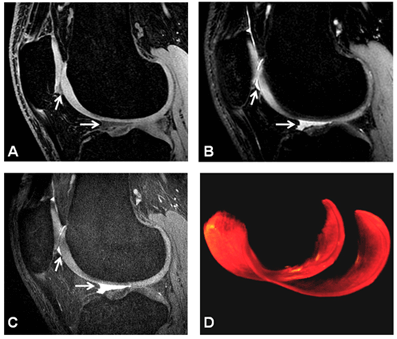

Kijowski and colleagues at UWM and Stanford University compared the new 3D fast spin-echo (FSE-Cube) sequence with a routine knee MRI protocol for evaluation of cartilage, ligaments, menisci, and osseous structures of the knee joint. The investigators enrolled 100 consecutive patients who underwent all MR scanning protocols at 3T using arthrography as the gold standard.

The researchers found that FSE-Cube provided volume measurements of the femoral, tibial, and patellar cartilage that led to detection of collateral ligament injuries and bone marrow edema lesions. FSE-Cube findings were just as diagnostically useful as those provided by the routine knee MRI protocol. The differences were not statistically significant. Kijowski released the group's findings at the 2008 RSNA meeting.

"FSE-Cube is an intermediate-weighted sequence with maximized signal-to-noise ratio efficiency, minimal blurring, and good fat suppression," Kijowski said. "It has similar diagnostic performance as a routine knee MRI protocol for evaluating the cartilage, ligaments, menisci, and osseous structures of the knee joint at 3T."